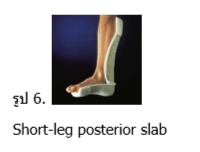

- การใส่เฝือกอ่อน (Short-leg posterior slab) (รูป 6) ขึ้นกับดุลพินิจของแพทย์